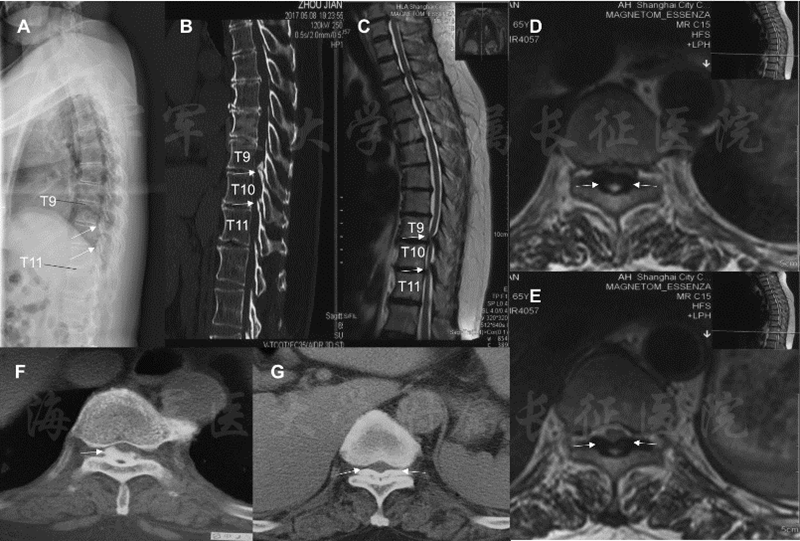

58岁女性患者,由于双下肢麻木、疼痛和行走障碍伴小便障碍两年,加重一月来我院就诊。术前X线片提示在T9/10h和T10/11处存在高密度影。进一步CT检查确诊为该节段黄韧带骨化,呈结节型和扩大型压迫脊髓,最高脊髓侵占率达71.61%(图5)。

图5 病人术前影像学资料